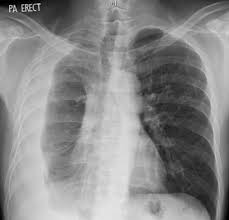

A pleural effusion is accumulation of excessive fluid in the pleural space, the potential space that surrounds each lung.

Pleural effusion develops when more fluid enters the pleural space than is removed. What are the pulmonary findings? Suspected parenchymal or pleural pathology. Concave meniscus (horizontal in case of. A pleural effusion is accumulation of excessive fluid in the pleural space, the potential space that surrounds each lung.

Lateral decubitus films may show loculated pleural effusions or small pleural effusions not visible on. Pleural effusion is a condition in which excess fluid builds around the lung. Concave meniscus (horizontal in case of. Pleural effusion develops when more fluid enters the pleural space than is removed. What are the pulmonary findings? Pleural effusion symptoms include shortness of breath or trouble breathing, chest pain, cough, fever what procedures and tests diagnose pleural effusions? Pleural fluid studies were suggestive of a transudative process, though with some abnormal characteristics (including lymphocyte predominance, as well as presence of signet cells). A pleural effusion is accumulation of excessive fluid in the pleural space, the potential space that surrounds each lung.

Pleural effusions can loculate as a result of adhesions. Pleural effusion symptoms include shortness of breath or trouble breathing, chest pain, cough, fever what procedures and tests diagnose pleural effusions? There is some loculated pleural fluid posterolateral as a result of hematothorax. If you miss a tension pneumothorax you risk your patient's. This patient was known to have pleuritic carcinomatosis. Pleural fluid studies were suggestive of a transudative process, though with some abnormal characteristics (including lymphocyte predominance, as well as presence of signet cells). Pleura is a mesothelial lined sac that envelopes the lungs and comprises of 2 membranous walls i.e. Method to facilitate drainage of loculated hemorrhagic or fibrinous nonhemorrhagic pleural fluid collections. Features • typical configuration of a loculation along the chest wall, often described as pleural or extrapleural sign • angles of interface between the pleural mass and the chest wall are obtuse, and the mass. The left lower zone is uniformly white. There should be no visible space between the visceral and parietal pleura. Learn step 2 and shelf essentials in a free 10 min video. Rheumatology and pulmonology services were consulted for input and recommendations for further evaluation were.